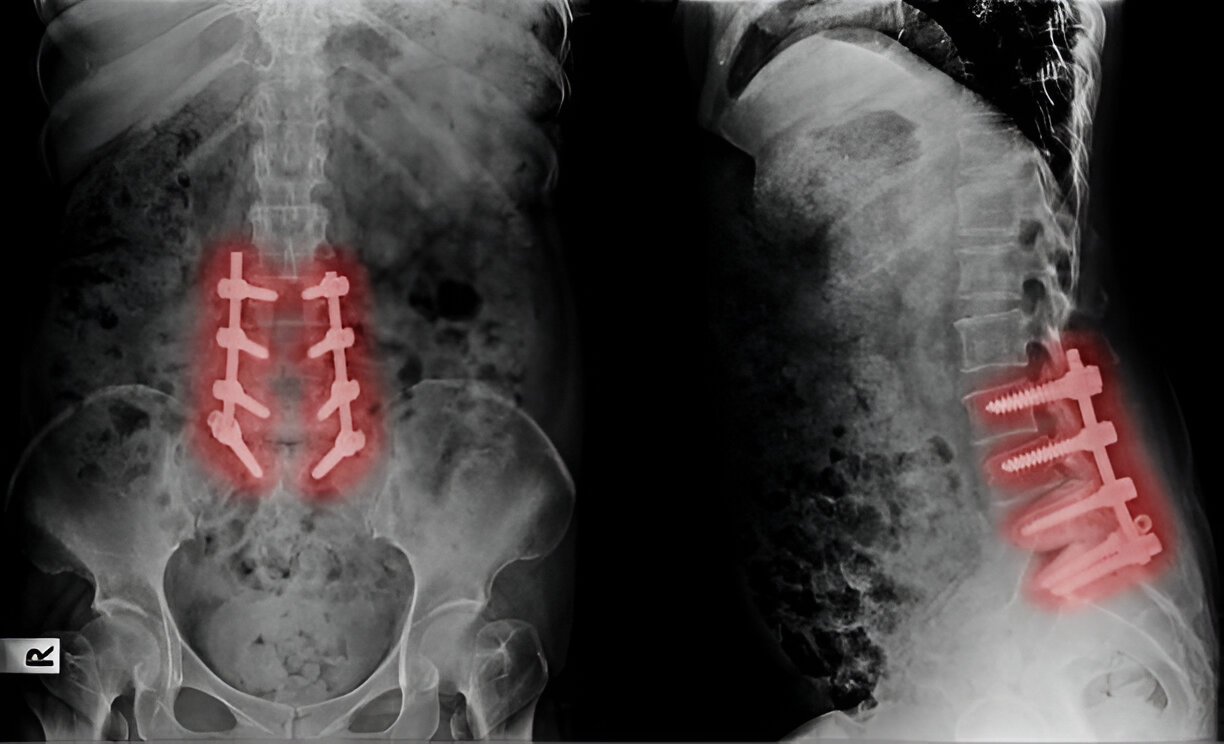

Spinal Fusion A procedure that stabilizes the spine by fusing two or more vertebrae together, often following an injury, degenerative disease, or after a decompression procedure.

- Stabilization of fractures, dislocations, and compression injuries.